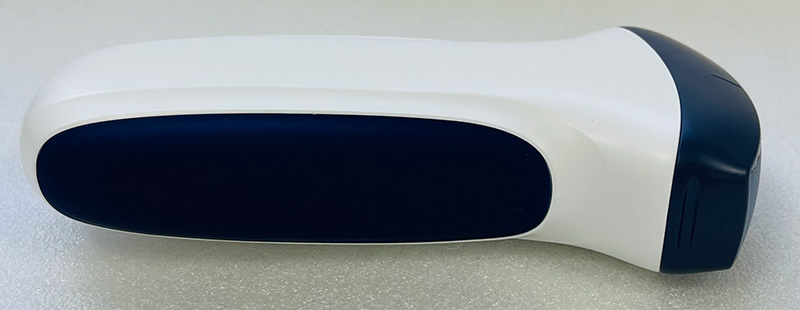

8C

8C Pro Series, larger battery version

8C Plus1 Series, larger battery version

8C Plus2 Series, larger battery version

8C Plus3 Series

• Size: 140mm×60mm×20mm

• Net Weight: 180 gram